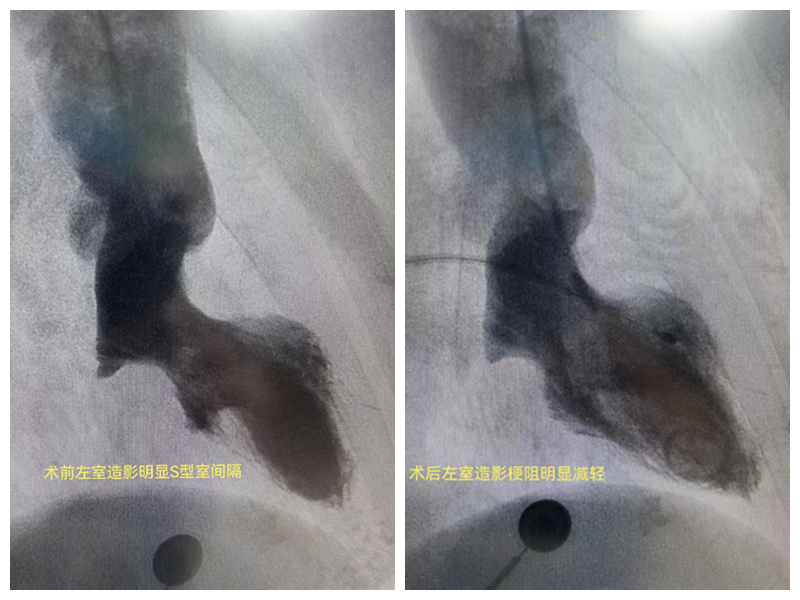

2月14日,手术正式开始。在超声科陈莞春主任的精准定位下,熊斌主任医师凭借多年的经验和精湛的技术,小心翼翼地将导管送入唐阿姨的体内。当导管到达预定位置时,无水酒精缓缓注入,团队成员紧盯着屏幕,密切关注着唐阿姨的各项生命体征。

终于,在经过2个小时的紧张操作后,手术成功完成!唐阿姨的左室流出道压力阶差从111mmHg降至5mmHg,血流速度从526cm/s降至148cm/s,手术效果立竿见影。术后,唐阿姨被转入CCU监护病房,生命体征平稳。当她醒来时,发现自己不再胸闷气短,呼吸也变得顺畅起来。那一刻,她的眼中充满了感激的泪水。